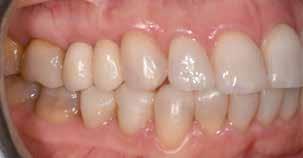

Hölgy páciensem az első konzultáció során tipikus kórtörténetet vázolt fel: Gyermekkora óta szeretett volna fogszabályozó készüléket, hiszen mindig is zavarta a class 2-es eltérésnél tipikusan jellemző nagy overjet (1-3. képek), és természetesen az ezáltal kifelé álló felső metszőfogai, részben a felső metszők protrúziója, részben pedig a disztálisan elhelyezkedő mandibula miatt. Annak ellenére, hogy több fogszabályozó szakorvosnál is járt az évek során, de mivel saggitális eltérése és az alsó metszőfogak torlódása miatt négy kisőrlőfog extrakcióját, illetve emellett sokszor állcsont műtétet is javasoltak neki, nem vágott bele a kezelésbe (4-5. képek).

A fogorvosa – nagyon helyesen – felhívta a figyelmét, hogy parodontális státusza is valószínűsíthetően romlani fog az eltérése miatt, újabb kört futott, immár 39 évesen, de még mindig premoláris fogak húzása és állcsontműtét nélkül szerette volna a fogszabályozást.

A konzultáció során arról is beszéltünk – ahogy az ilyenkor lenni szokott –, sohasem szeretett igazán mosolyogni, de a Pitts Protokolloknak köszönhetően az arc- és mosolyesztétikai céloknak megfelelően kerül megvalósításra az okklúziós korrekció. Az okklúziós kezelési célok az alábbiak voltak: a felső és alsó fogív nivellálása és tágítása, az alsó fogsor/ mandibula mezializálása, valamint a harapás megemelése által a mélyharapás rendezése.